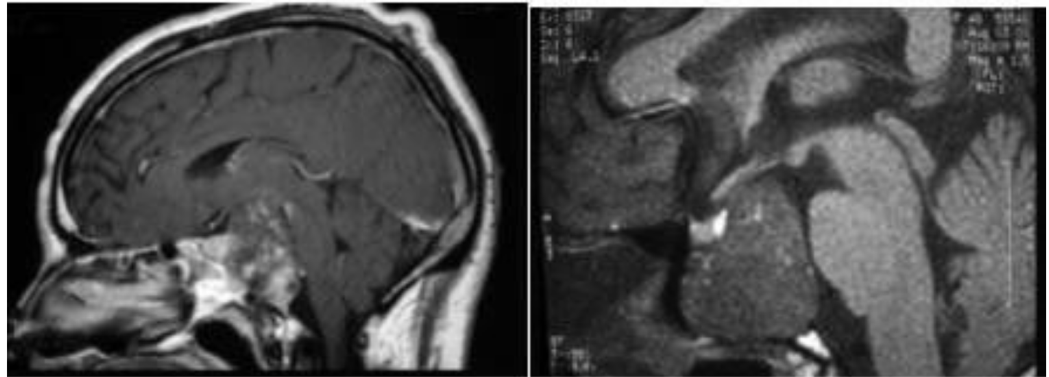

患者40+岁,女性,患者临床症状明显,近1年多来相继头痛、复视、肢体无力、吞咽困难等,当地医院诊断为较大斜坡脑膜瘤,辗转多地医院均告知肿瘤无法全切,术后并发症风险发生率高,后慕名咨询德国国际神经科学中心INI寻求巴特朗菲手术治疗,肿瘤切除97%以上,无相关手术并发症。

术前MR示:斜坡较大脑膜瘤,压迫脑干、颅神经,侵犯基底动脉等